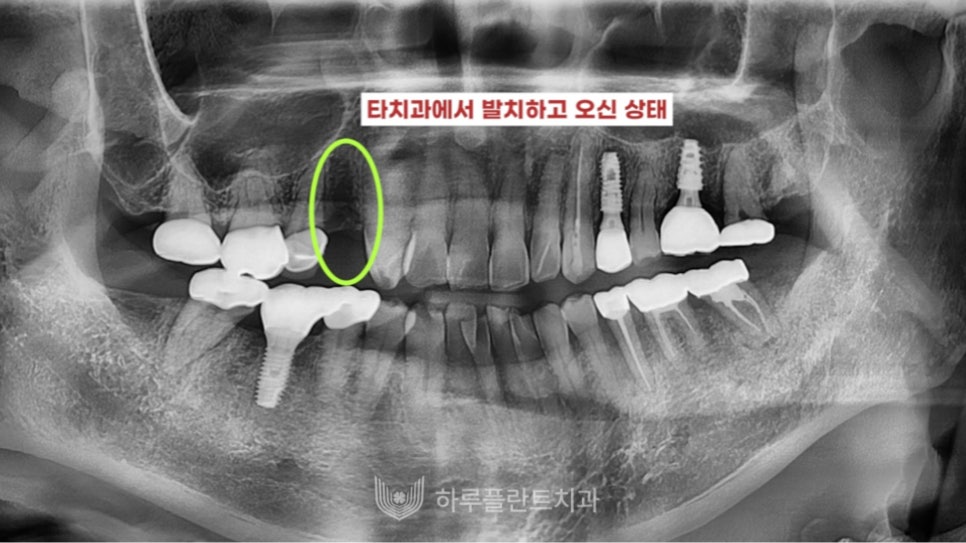

강남구 당일 임플란트 성공 케이스 1

23.05

타 치과에서 발치를 한 상태로

저희 하루플란트치과를 찾아오셨습니다.

무절개 당일 임플란트를 진행했는데요,

진단 드릴링 후 진단핀을 꽂아

위치를 3차원적으로 확인 후

위치나 각도를 세밀하게 확인하여

성공적으로 식립을 마무리했습니다.

무절개로 진행하여 출혈, 통증 없이

편안한 과정으로 수술을 마쳤습니다.